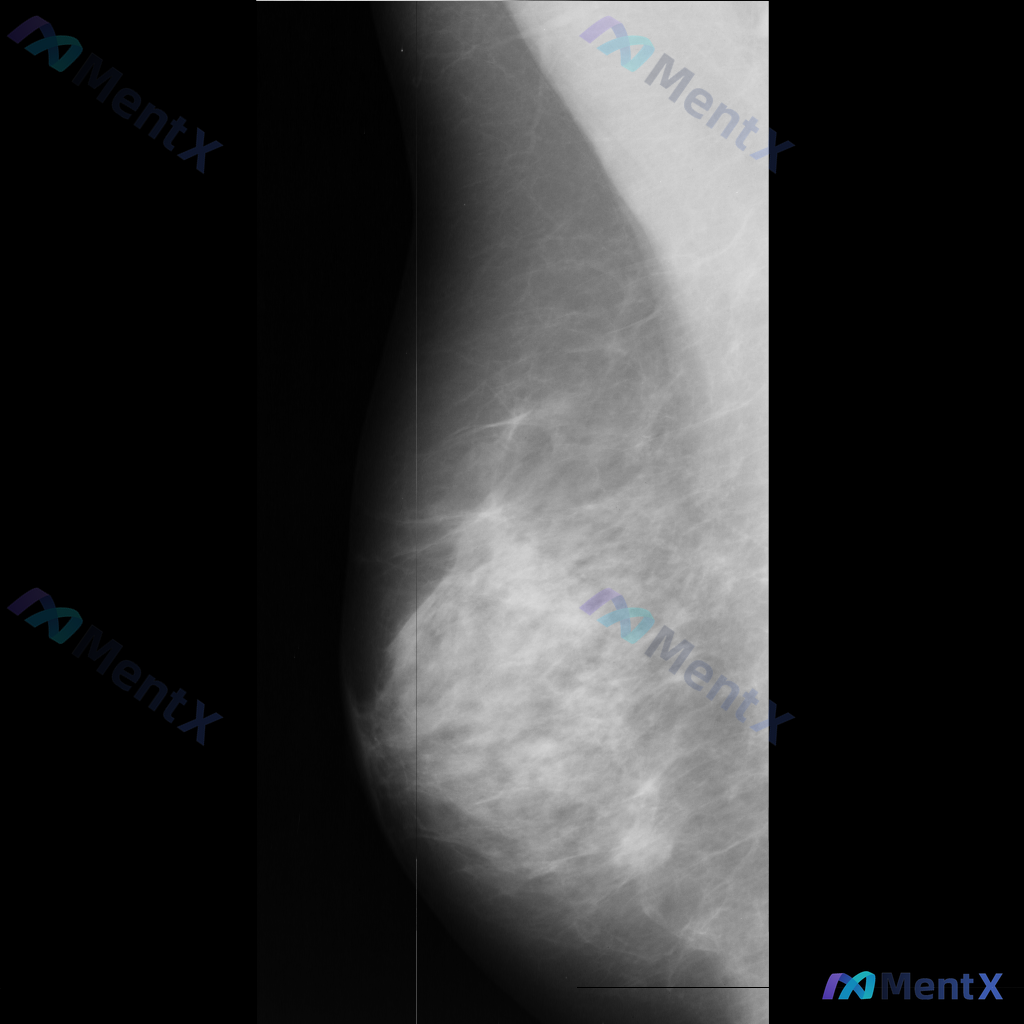

这张左乳MLO位X光片的异常表现,你会怎么考虑?

整理到一份乳腺影像资料,和大家讨论一下读片后的判断方向。 基本影像信息 - 体位:左乳内外斜位(MLO) - 影像质量:曝光和对比度良好,胸大肌边缘可见,无明显技术伪影 - 乳腺组织构成:散在纤维腺体/不均匀致密型 主要影像表现 在左乳头后方、乳晕附近,可见一类圆形/卵圆形密度增高影: - 边界似清...